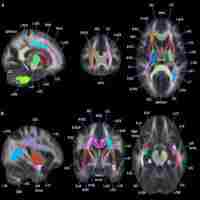

| Abstract | Diffusion tensor imaging (DTI) tractography and functional magnetic resonance imaging (fMRI) are powerful techniques to elucidate the anatomical and functional aspects of brain connectivity. However, integrating these approaches to describe the precise link between structure and function within specific brain circuits remains challenging. In this study, a novel DTI–fMRI integration method is proposed, to provide the topographical characterization and the volumetric assessment of the functional and anatomical connections within the language circuit. In a group of 21 healthy elderly subjects (mean age 68.5 ± 5.8 years), the volume of connection between the cortical activity elicited by a verbal fluency task and the cortico-cortical fiber tracts associated with this function are mapped and quantified. An application of the method to a case study in neuro-rehabilitation context is also presented. Integrating structural and functional data within the same framework, this approach provides an overall view of white and gray matter when studying specific brain circuits. |